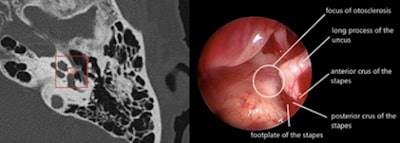

Oto-Med / Surgery agreement in a patient operated on for left stapedial otosclerosis. Figure courtesy of Dr. Arnaud Attyé, Grenoble University Hospital Center, France.

Oto-Med / Surgery agreement in a patient operated on for left stapedial otosclerosis. Figure courtesy of Dr. Arnaud Attyé, Grenoble University Hospital Center, France.It is also the integration of these technologies into everyday tools and in particular into PACS that will allow their development and easy routine use. This is crucial for the acceptance of these new tools. It is necessary to be able to access the analysis without changing environment and with a maximum response time of no more than a minute for routine clinical use.